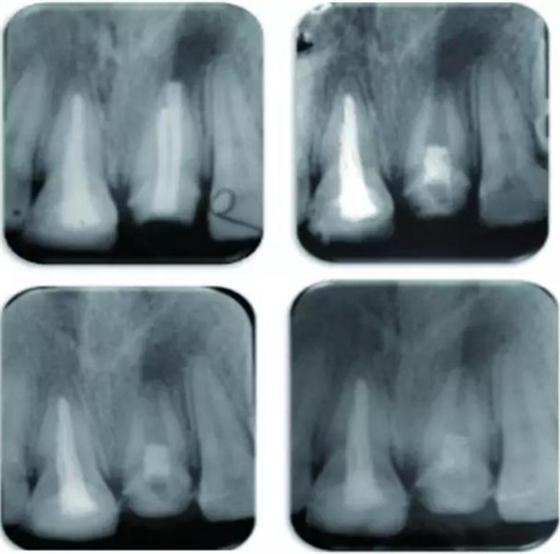

例為兩名年齡分別為26歲和12歲的男性患者,各有一顆恒牙(牙位分別為21與35)因患有根管治療后持續(xù)性根尖周炎而需進(jìn)行再治療。用Carvene 牙膠溶解劑和ProTaper普通旋轉(zhuǎn)式再治療根管銼去除患牙根管內(nèi)充填的牙膠,接著進(jìn)一步用旋轉(zhuǎn)再治療銼和大量次氯酸鈉對(duì)根管進(jìn)行化學(xué)機(jī)械法清理,然后用Metapaste 干燥根管。對(duì)21和35兩患牙進(jìn)行牙髓再生術(shù)治療。將根尖周的出血引入消毒后的根管內(nèi),用礦物三氧化物聚合物(MTA)填料覆蓋血塊,根管口修復(fù)材料填充。

結(jié)果為,兩患牙分別在隨訪13個(gè)月及14個(gè)月時(shí)表現(xiàn)出根尖周炎的臨床恢復(fù)體征和/或癥狀。21患牙顯示出根管變窄以及根尖部硬組織沉積而形成根尖封閉。

圖 21治療全過(guò)程,圖A 為治療前根尖片,圖B 為術(shù)后根尖片,圖C 顯示治療7 個(gè)月后根尖陰影縮小,圖D顯示治療后13個(gè)月根管口變窄